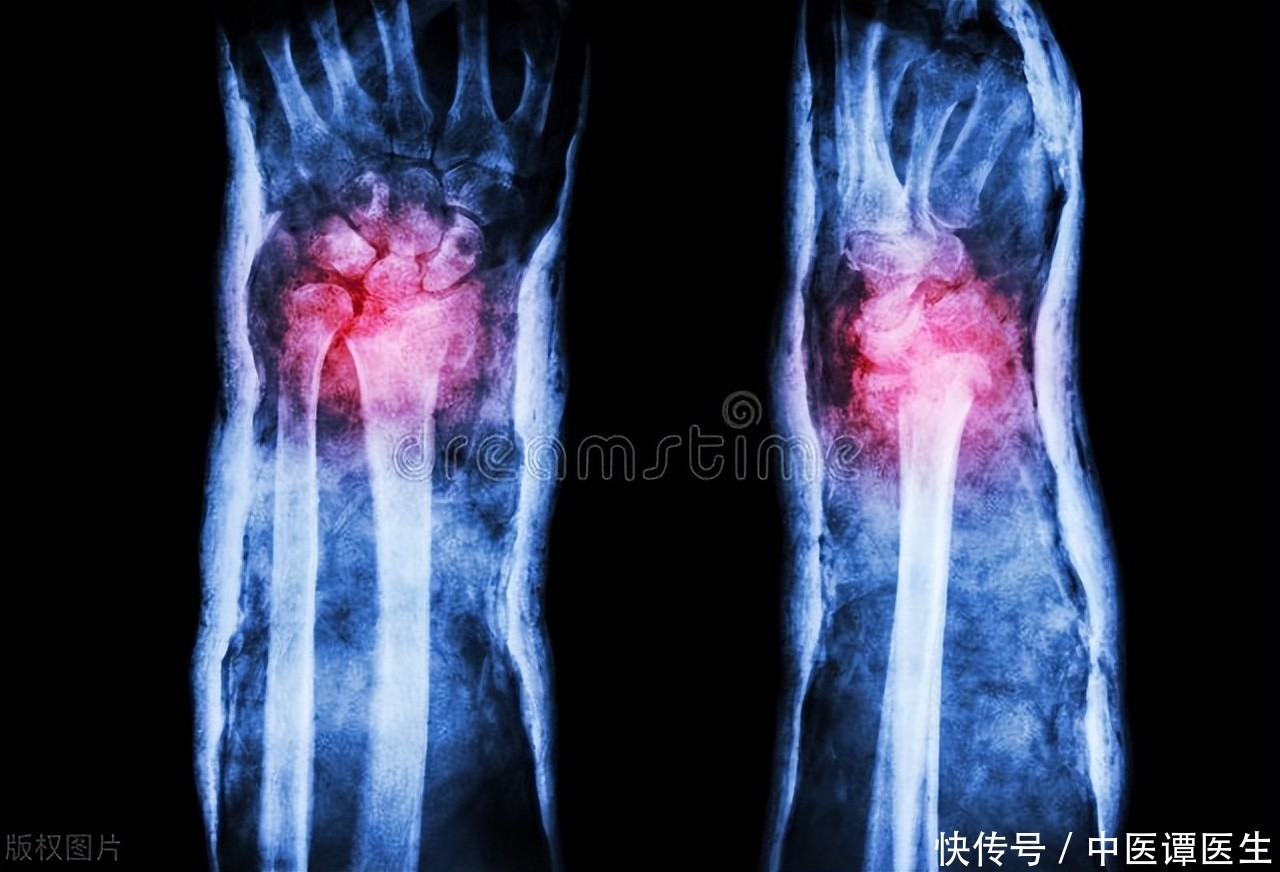

X线影像作为最为常用的影像学检查方法之一,对于骨质疏松的诊断作用却并不如我们想象中的直观。在初期,骨骼脆弱往往“悄然无息”,病患一般不会显现出显著迹象,直至遭遇骨裂之时方被察觉。原因在于,骨质疏松是骨密度下降、骨小梁变薄的一个渐进过程,X线虽然能显示骨密度的变化,但这种变化通常较为隐匿,尤其是在早期,骨骼的变化未必足够显著,导致X线很难作为单一的诊断工具。

放射线检测可以捕捉到骨质疏松的“微妙迹象”,这主要体现在骨骼密度的减少以及骨小梁构造的变化之上。当骨骼出现显著的空洞或变得疏松,X线影像才会表现出比较明显的骨密度减低特征。但如果骨质疏松处于早期,很多时候X线无法明确显示出具体的骨质变化。骨密度检测(DXA)通常被认为是诊断骨质疏松的更为准确方法,尤其是在没有骨折的情况下。

骨质软化的一个关键表现是骨骼的形态发生变化。鉴于骨骼缺乏足够的硬度,它们易于发生形变,或许会产生异常形态、歪曲等状况,特别是在承受重量的区域,诸如脊椎、下肢骨骼等地方。病患或许展现出步行受阻,肢体呈现弯曲形态或脊椎结构不正常的症状。虽然X线能够帮助识别这些骨骼的形态变化,但仅凭X线影像很难判断是否为骨质软化,通常需要结合血液检查和骨密度检测来做进一步确认。

虽然X线在临床上被广泛应用于骨科诊断,但它在骨质疏松和骨质软化的诊断中都有一定的局限性。在骨质疏松的早期,X线可能未能显现出足够明显的骨密度下降,而在骨质软化中,X线更多地依赖于骨形态的改变,难以准确反映骨矿化状态。X线影像作为单一检查手段,无法提供足够的信息来诊断这两种疾病,结合其他检查手段如CT、MRI、骨密度检测以及血液生化检查,会更为有效。